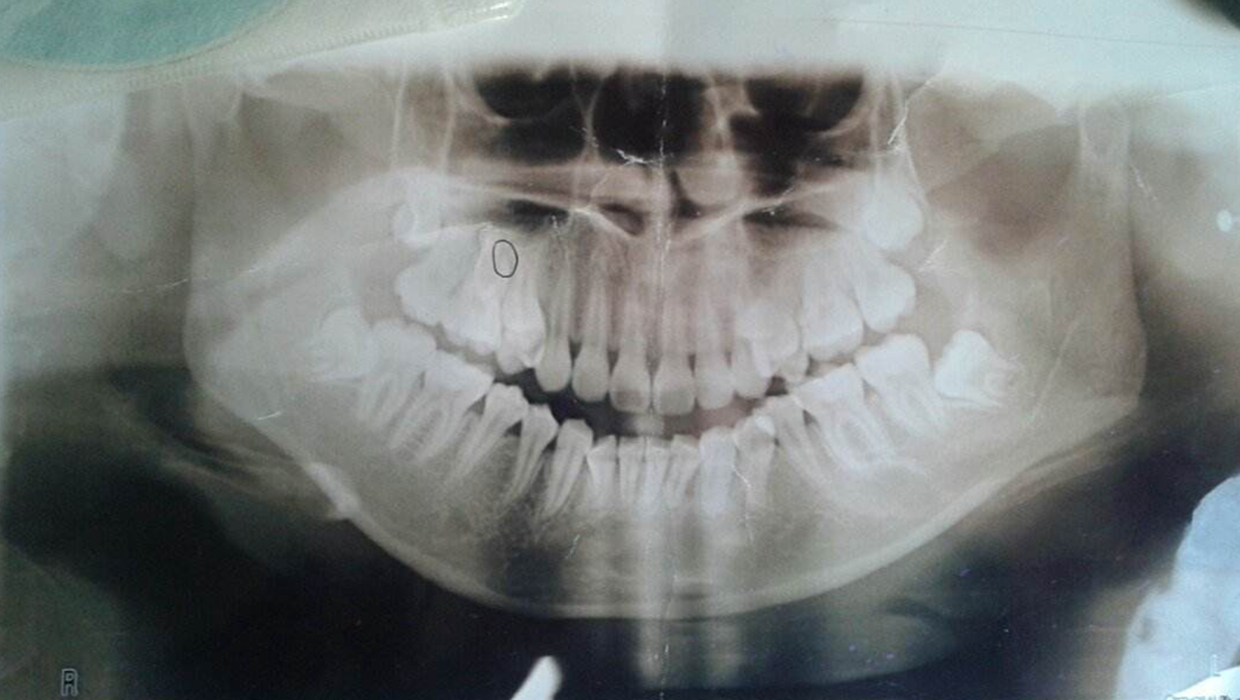

请懂得牙科医生看看,我有个门牙有点外突,不知道能不能弄弄,别再突了

骨性牙凸,?

这样算是牙槽骨突出吗?

大夫您好,我今年27岁了,我的嘴有点鼓,牙床突出,门牙有点大,也突.

问题:上牙床突出要怎么治疗?

因为牙槽骨前突,露龈笑,下嘴唇外翻,颏唇沟消失,下巴后缩,下巴短小